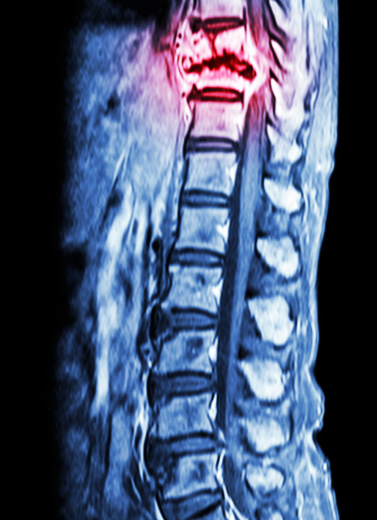

Spinal Fractures & Trauma

Chronic Back Pain